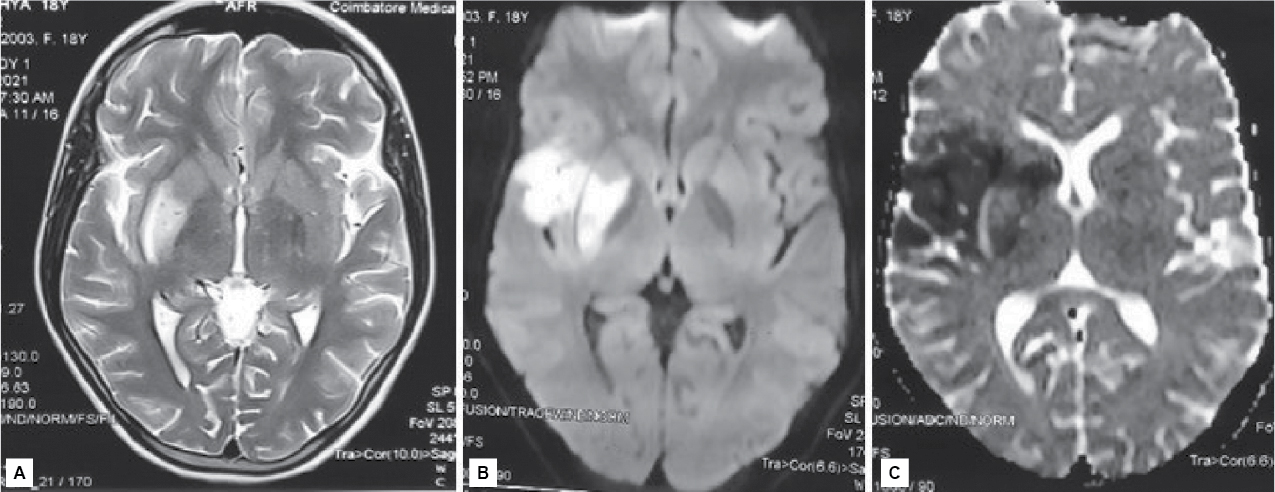

MRI of brain showed acute infarct in right frontal lobe, right caudate nucleus, lentiform nucleus and right corona radiata (Fig. 1). Magnetic resonance angiogram (MRA) of intracranial vessels showed nonvisualization of intracranial part of right internal carotid artery and complete reformation of right anterior cerebral artery (Fig. 2).

Figure 1. MRI of brain – A) T2/FLAIR; B) Diffusion-weighted imaging showing hyperintensity in right insular cortex and right lentiform nucleus; C) Attenuated diffusion coefficient showing hypodensity in the right gangliocapsular area, right insular cortex and caudate.